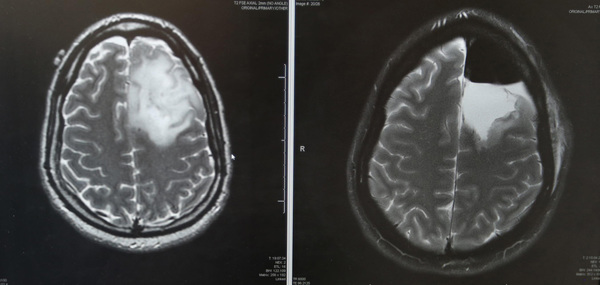

In mid-April, Hartsfield, 30, underwent a craniotomy to remove a fist-sized brain tumor _ while he was awake. The tumor was located near the part of the brain that controls movement and language, so surgeons had to keep him singing, talking, counting and wiggling his arms and legs throughout the hours-long procedure at the University of Miami Hospital to make sure they weren't damaging his brain.